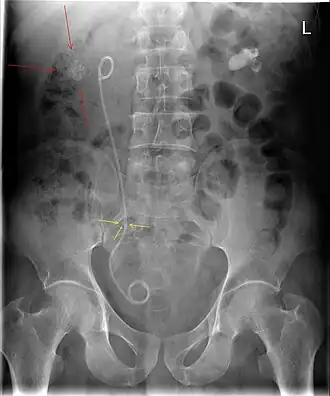

Röntgenfoto van de buik met beiderzijds een 'niersteen. Rechts, links op de afbeelding, zijn meerdere nierstenen zichtbaar (Zie rode pijlen). De grote witte vlek links, (rechts op de afbeelding) is één grote steen, vaak aangeduid met de naam 'koraalsteen' of 'afgietselsteen'. Verder is er ook een steen zichtbaar in de rechter urineleider (zie gele pijlen). Ter behandeling van de hierdoor optredende ureterstenose is er een dubbel-J katheter geplaatst.